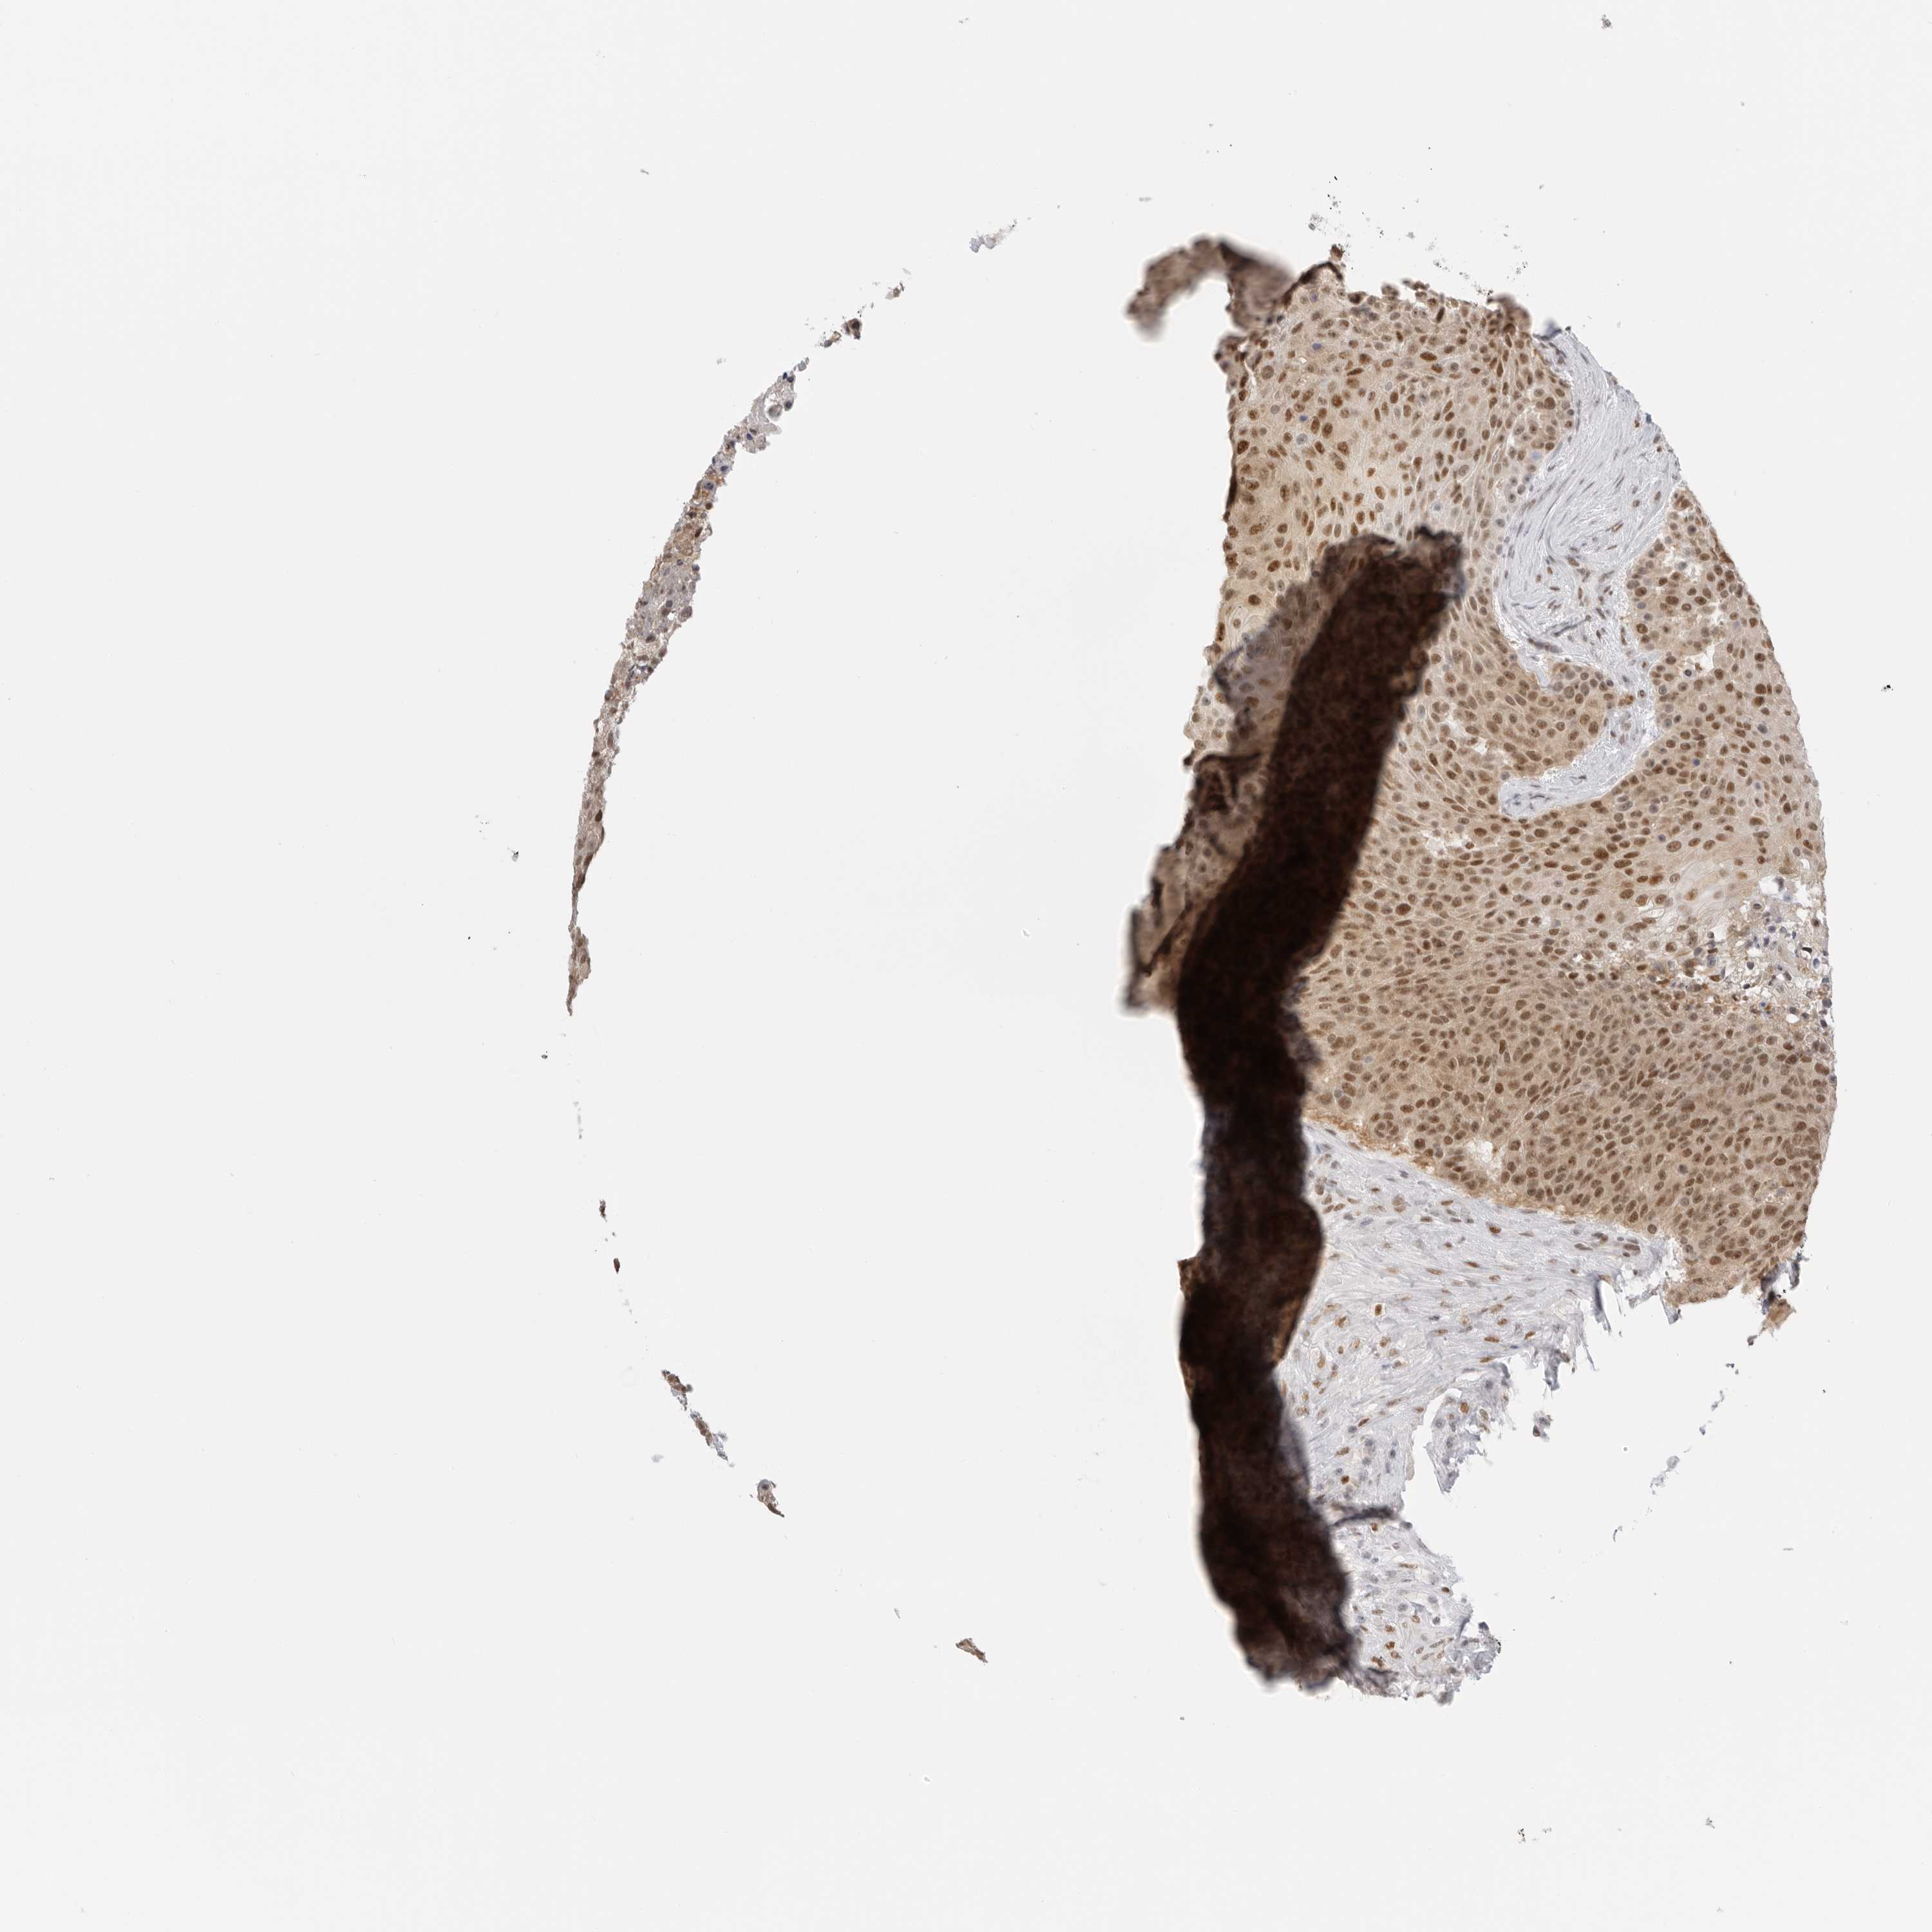

UROTHELIAL CANCER - Protein expressioni

A mouse-over function shows sample information and annotation data. Click on an image to view it in a full screen mode. Samples can be filtered based on level of antibody staining by selecting one or several of the following categories: high, medium, low and not detected. The assay and annotation is described here.

Note that samples used for immunohistochemistry by the Human Protein Atlas do not correspond to samples in the TCGA dataset.

Antibody stainingi

Antibody staining in the annotated cell types in the current human tissue is reported as not detected, low, medium, or high, based on conventional immunohistochemistry profiling in selected tissues. This score is based on the combination of the staining intensity and fraction of stained cells.

Each image is clickable and will lead to virtual microscopy that enables deeper exploration of all samples and also displays staining intensity scores, fraction scores and subcellular localization as well as patient and tissue information for each sample.

Antibody HPA026306

Antibody HPA026309

Antibody CAB016538

Staining

High

Medium

Low

Not detected

Intensity

Strong

Moderate

Weak

Negative

Quantity

>75%

75%-25%

<25%

None

Location

Nuclear

Cytoplasmic/membranous

Cytoplasmic/membranous,nuclear

Urothelial carcinoma, Low grade

Urothelial carcinoma, High grade